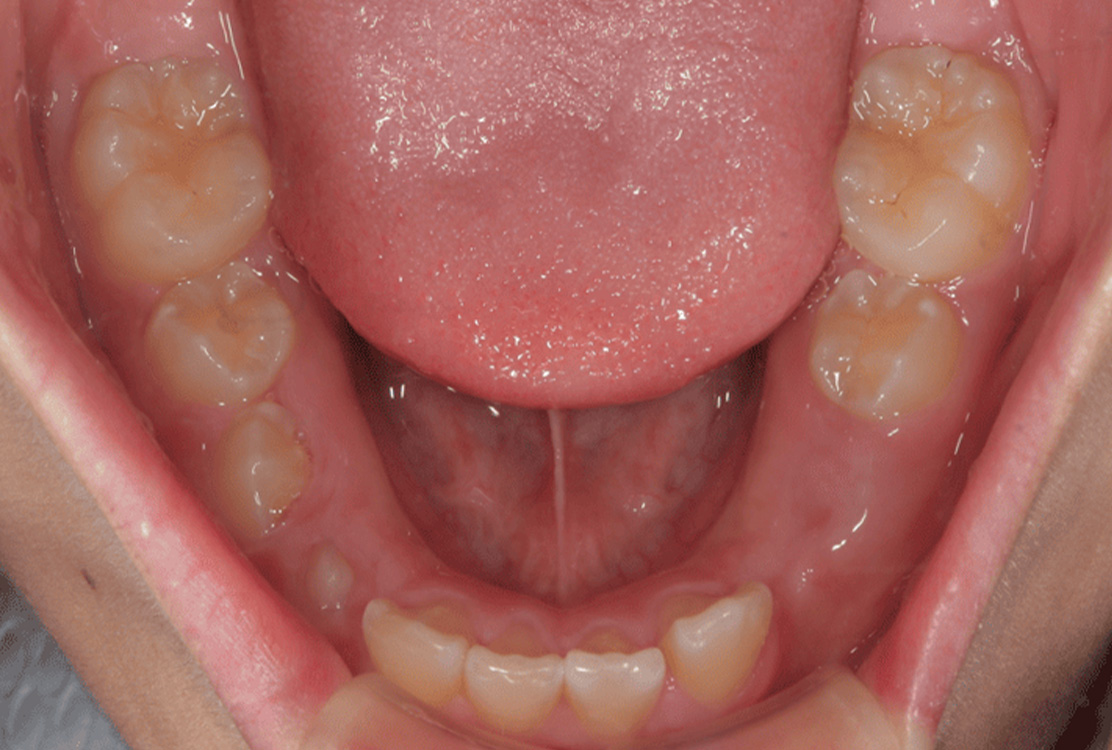

治療前